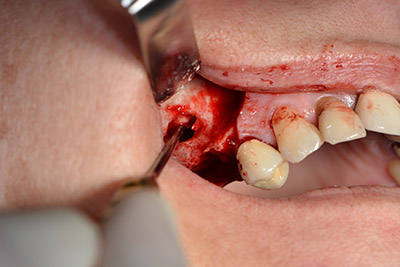

Die klassische Schnittführung (krestal, Entlastung bukkal) und das Präparieren des Mukoperiostlappens erlauben eine gute Übersicht.

Danach wird das Implantat eingebracht und der Knochen aufgebaut. Aufgrund der Größe des Augmentates wurde im vorliegenden Fall Eigenknochen, der als Bohrspäne bei der Implantation 16 und der Fenestration 14 angefallen ist und mit einer Knochenfalle aufgefangen wurde, mit Knochenersatzmaterial vermischt.

Eine resorbierbare Membran bildet die Barriere nach bukkal und deckt das Augmentat ab. Zum Schluss wird speicheldicht vernäht. (Abb. 15 bis 19).